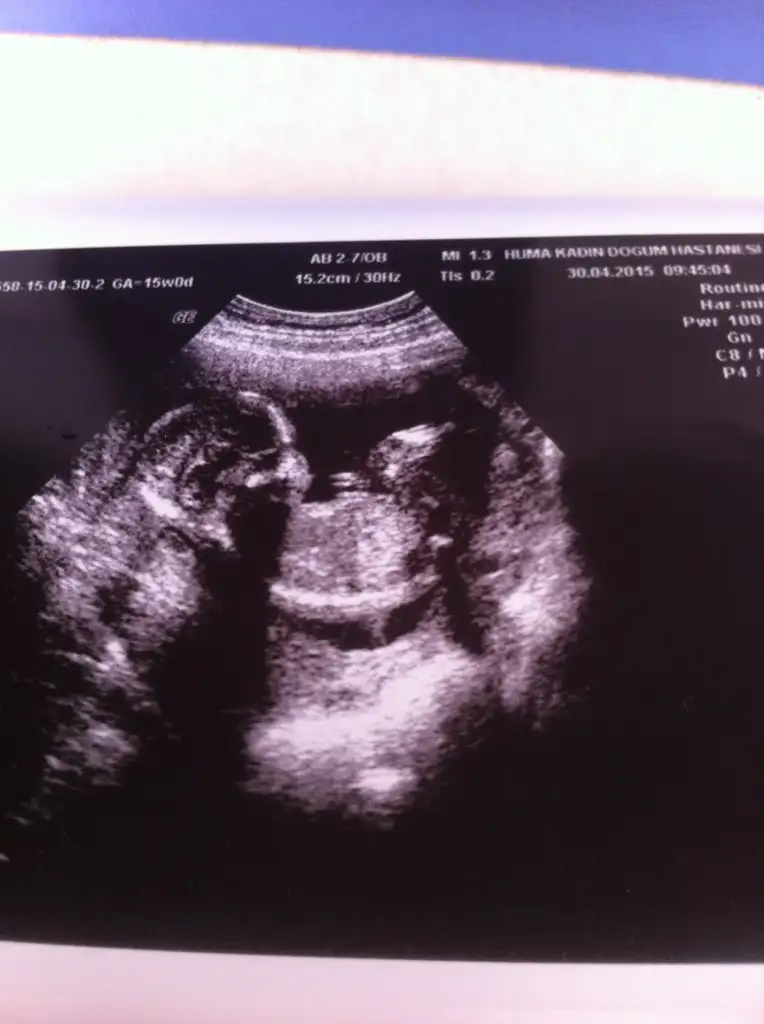

mrb arkadaşlar bugün 15 haftalık olduk kontrol vardı ve cinsiyetimize %51 den yüksek erkek dedi. resimler kalitesiz diyende var siz anlayabilirmisiniz merak beni öldürecek :)